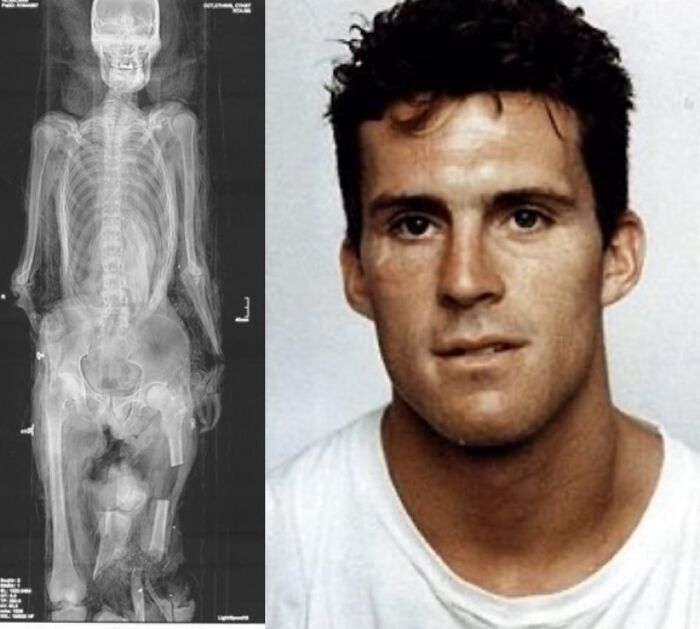

An X-ray showing Robbie Knievel’s spine and an actual photograph of the metal device after he passed away in January 2023.